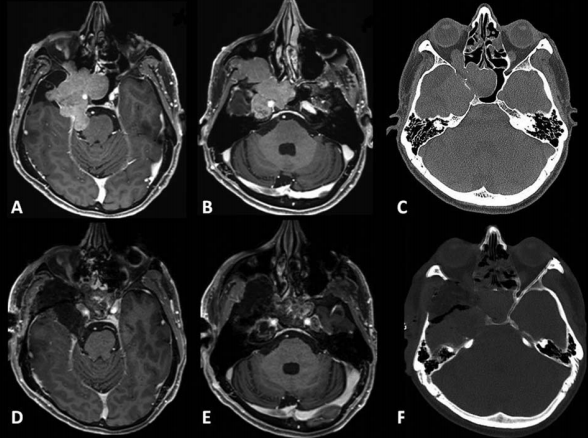

术前术后影像对比:(A)术前MRI显示脑膜瘤延伸至后颅窝(PF)、海绵窦(CS)、眼眶和蝶窦(SS)。(B)肿瘤延伸至中窝、翼腭窝(PPF)和颞下窝(ITF)。(C)术前CT显示更大的蝶翼侵蚀和蝶窦受累。(D,E)术后MRI显示肿瘤完全切除。(F)术后轴位CT扫描显示用于闭合的脂肪移植物。

案例来源:Sébastien Froelich.Endoscopic-Assisted Microsurgical Resection of Right Recurrent Meckel's Cave Meningioma Extended to Cavernous Sinus.J Neurol Surg B Skull Base.2021 May 11;83(Suppl 3):e632–e634.doi:10.1055/s-0041-1725934